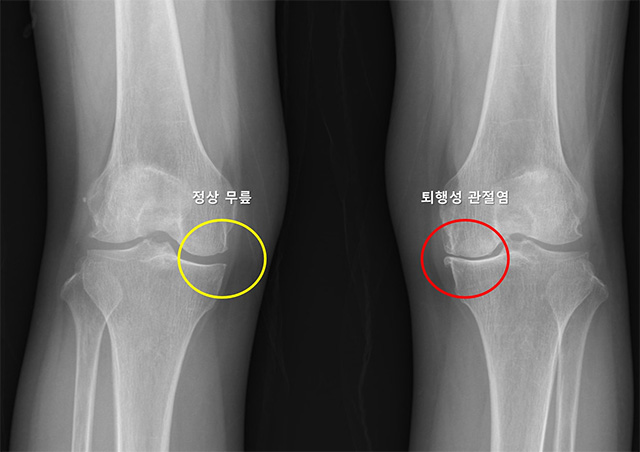

▲ X-ray 이미지. 정상 무릎(노란색)은 관절 간격이 잘 유지되고 뼈 모양이 정상이며, 퇴행성 관절염(빨간색)은 관절 간격이 좁아지고 뼈 모양이 변형됨. /이미지 제공=서울대병원